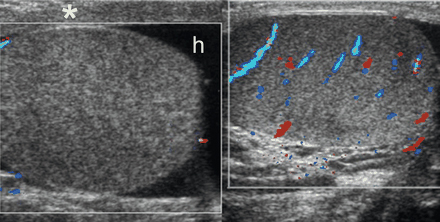

[Figure caption and citation for the preceding image starts]: Bilateral transverse colour Doppler images in a 12-year-old boy with right-sided scrotal pain of sudden onset, showing no colour flow signals in the right testis, which is enlarged and has heterogeneous echogenicity; reactive hydrocele (h) and thickening of the scrotal wall (*) are also seen; testicular torsion and bell clapper deformity were confirmed at surgeryAso C, et al. RadioGraphics. 2005;25:1197-1214. Used with permission [Citation ends].

Colour Doppler and/or power Doppler studies are also needed to establish the presence or absence of blood flow to the testicles.[29]Sparano A, Acampora C, Scaglione M, et al. Using color power Doppler ultrasound imaging to diagnose the acute scrotum. A pictorial essay. Emerg Radiol. 2008 Sep;15(5):289-94.

Power Doppler is more sensitive to low blood flow than regular colour Doppler.[32]Expert Panel on Urological Imaging, Gerena M, Allen BC, et al. ACR appropriateness criteria® acute onset of scrotal pain-without trauma, without antecedent mass: 2024 update. J Am Coll Radiol. 2024 Nov;21(11s):S364-71.

Normal or increased intra-testicular blood flow (i.e., hyperaemia) may suggest an inflammatory diagnosis or successful de-torsion.[29]Sparano A, Acampora C, Scaglione M, et al. Using color power Doppler ultrasound imaging to diagnose the acute scrotum. A pictorial essay. Emerg Radiol. 2008 Sep;15(5):289-94.

However, blood flow does not exclude a diagnosis of testicular torsion because arterial flow may be present in early phases of torsion, or in partial or intermittent torsion. Comparison with the contralateral testicle should be carried out to identify differences in flow.[24]European Association of Urology. Paediatric urology. Apr 2024 [internet publication].